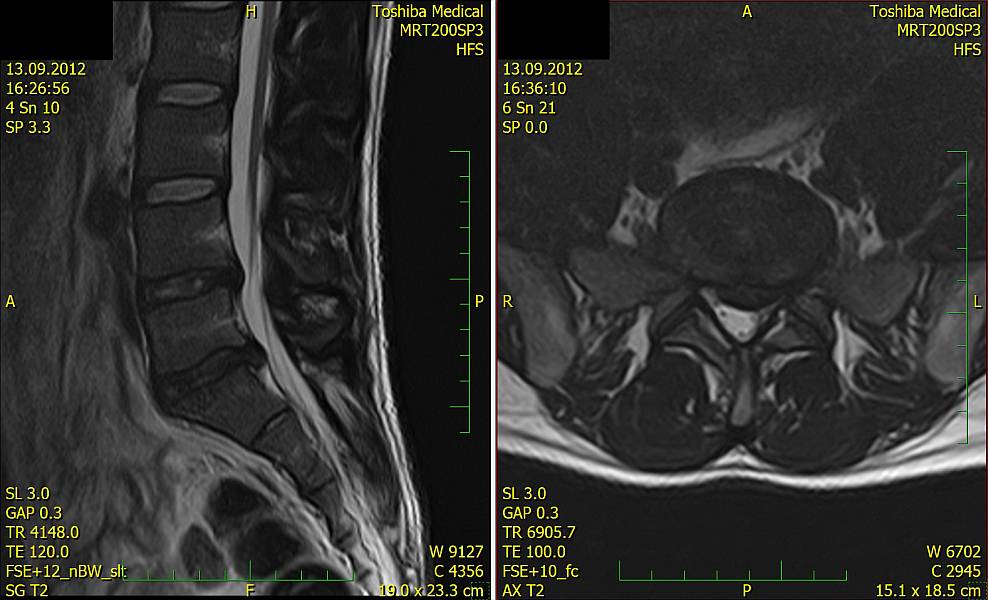

2. Muž, 41 let. Na MR objemná hernie L4/5 velikosti 11mm téměř vyplňující páteřní kanál, útlak nervových kořenů. Opakovaně doporučována operace, kterou pacient odmítl. Jako alternativu zvolil ozonoterapii s aplikací ozonu do disku L4/5 a periradikulárně. Byly aplikovány celkem 3 dávky ozonu. Viz obr.7a

Na kontrolním MR po 6 měsících je patrná výrazná redukce velikosti hernie, vymizely fragmenty, uvolnil se páteřní kanál a do značné míry i nervové kořeny. Subjektivně výrazná úleva téměř k normálu. Viz obr. 7b